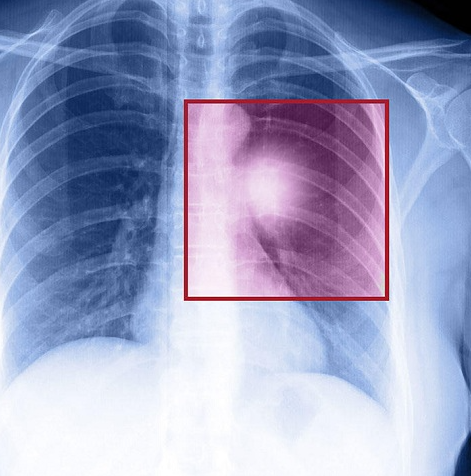

Tỷ lệ sống sau 5 năm: 9.2%

Nguy cơ mắc bệnh: 1/140 đối với nam giới, 1/710 đối với nữ giới

Phổi, tim và nhiều cơ quan khác trong cơ thể đều được bao bọc bởi một lớp mô mỏng gọi là trung mô. Do vậy u trung biểu mô là căn bệnh ung thư lớp mô phủ bên trong lồng ngực hoặc ổ bụng.

Theo một nghiên cứu tại Australia, khoảng 80% các trường hợp mắc bệnh là do hít phải sợi amiăng. Những người làm ngành nghề xây dựng, lắp đặt ống nước là nhóm đối tượng có nguy cơ cao nhất.

Các triệu chứng có thể bao gồm đau ngực, thở gấp, đau và sưng vùng bụng phụ thuộc vào vị trí của ung thư.